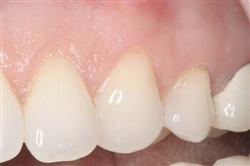

Normally gum tissue surrounds and protects the delicate roots of your teeth. Exposed tooth roots are prone to tooth decay, root canals, discoloration and actual jawbone loss. All of this can lead to tooth loss in advanced cases.

Functional Soft Tissue Grafting replaces the missing gum tissue and protects your teeth. For this reason, soft tissue grafting may be recommended even for back teeth.